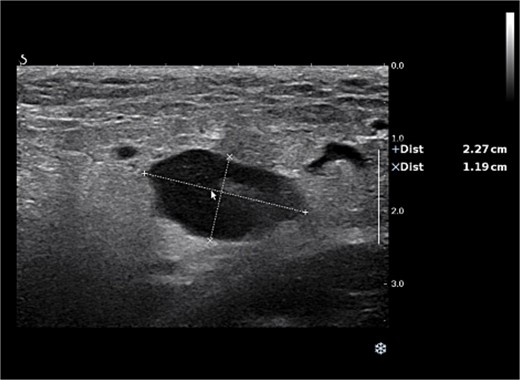

Examination revealed significant enlargement and tenderness of the right inguinal lymph node compared with previous assessments, while no other enlarged lymph nodes were palpated in regions such as behind the ear, under the jaw, under the clavicle, or in the left inguinal area. Measuring 23 × 12 mm on ultrasound, without abnormal blood flow on Color Doppler Flow Imaging (Fig. 3).